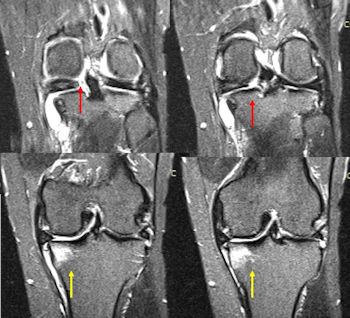

Kök yırtığının tanısı dikkatli bir hastalık hikayesi alınması ve muayene ile başlar. Doktorunuz, muayene sırasında menisküs yırtığı yanında, tedaviyi etkileyebilecek bacak şekil bozuklukları, diz bağlarının durumu ve dizde aşınma miktarının saptanmasına yönelik incelemeler yapar. Röntgen grafileri ile bacağın dizilimi ve dizdeki artroz miktarı değerlendirilir. Doktorunuz, kalça diz ve ayak bileğini içeren ve aks grafisi adı verilen özel röntgen grafileri ile bacak dizilimi ve yük aksının nereden geçtiğini değerlendirmek isteyebilir.Menisküs kök yırtıklarının tanısında en değerli yöntem manyetik rezonans görüntülemedir (MRG). MRG ile alınan özel koronal kesitler ile tanı doğrulanır. Ayrıca menisküsün eklem dışına itilme miktarı, kemik ödemi olup olmadığı ve dizdeki aşınmanın miktarı değerlendirilir. (Resim 2).